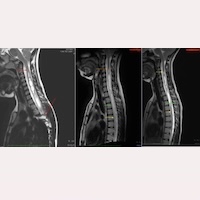

Fig.1 Comparative follow-up of C.: magnetic resonance imaging (25/03/2015 – 15/05/2023 – 19/03/2025)

In her comparative MRI follow-up, the following can be observed:

- In the first preoperative image of Fig.1 (25/03/2015), red arrows are visible. The upper arrow indicates the beginning of the intramedullary cavity at C1, and the lower arrow points to the dorsal scoliosis, which prevents visualisation of the spinal cord.

- In the second image, from her follow-up 8 years after the operation (MRI dated 15/05/2023), there is an improvement in the syringomyelic cavity, along with the disappearance of the dorsal scoliosis.

- In the third image, from her 10-year follow-up after the SFT (MRI dated 19/03/2025), the improvement of the intramedullary cyst continues favourably, with the cavity becoming increasingly filiform.